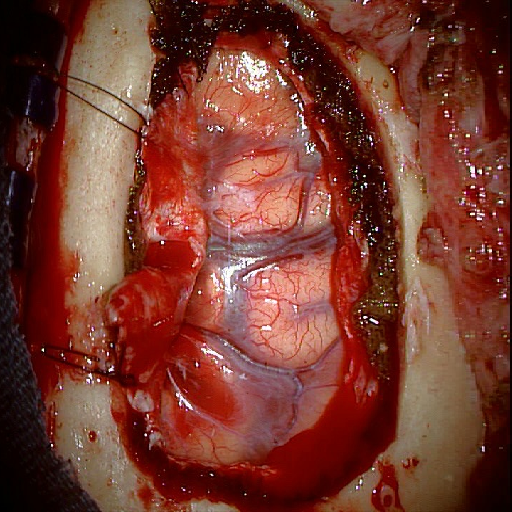

We tested our method retrospectively on 6 clinical datasets from 6 patients (cases) (see Fig. 5). These consisted of preoperative T1 contrast MRI scans and intraoperative images of the brain surface after dura opening. Cortical vessels around the tumors were segmented and triangulated to generate 3D meshes using 3D Slicer. We generated 100 poses for each 3D mesh (i.e.: each case) and used a total of 15 unique textures from human brain surfaces (different from our 6 clinical datasets) for synthesis using . In order to account for potential intraoperative brain deformations [4] we augment the textured projection with elastic deformation [21] resulting in approximately 1500 images per case. The surgical images of the brain (left image of the stereoscopic camera) were acquired with a Carl Zeiss surgical microscope. The ground-truth poses were obtained by manually aligning the 3D meshes on their corresponding images.

Fig. 5 shows our results as Augmented Reality views with bounding boxes and overlaid meshes. Our method produced visually consistent alignments for all 6 clinical cases without the need for initial registration. Because our current method does not account for brain-shift deformation, our method produced some misalignment errors. However, in all cases, our predictions are similar to the ground truth.